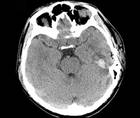

Challenge Case Report: PostCOVID-19 Encephalitis

Meghan Grassel, MS; Abdul R. Alchaki, MDMeghan Grassel, MS; Abdul R. Alchaki, MD - MS & Immune Disorders